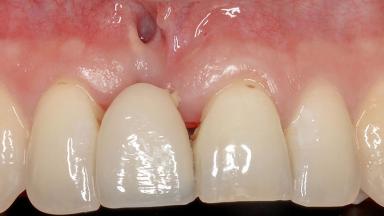

In this case, Shakeel Shahdad employs a two-layer matrix to repair a soft-tissue defect in a post-extraction healed site prior to implant placement with simultaneous guided bone regeneration. This approach resulted in a gain of keratinized peri-implant mucosa with optimal shade and texture. Soft-tissue defects are often encountered prior to implant placement and may result in deficient attached keratinized mucosa, which unless corrected will yield less than ideal esthetic outcomes. The presence of keratinized mucosa has been proposed as one of the prognostic factors for the survival of dental implants (Adell and coworkers 1986) with reported greater reductions in gingival and plaque indices after increasing the width of keratinized mucosa by soft-tissue augmentation (Giannobile and coworkers 2018; Thoma and coworkers 2018).